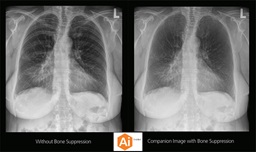

Upgrading your imaging system to a solution designed for outstanding image quality is no longer out of reach — it's now easier, more affordable, and more effective than ever before.

Our Carestream Focus HD 35/43 Retrofit Detectors, powered by Image Suite Software, are an ideal solution to step up to full digital X-ray for customers who simply cannot compromise on image quality. It seamlessly integrates into existing setups, bringing the power of full digital X-ray with minimal disruption and maximum clarity, along with the following benefits: